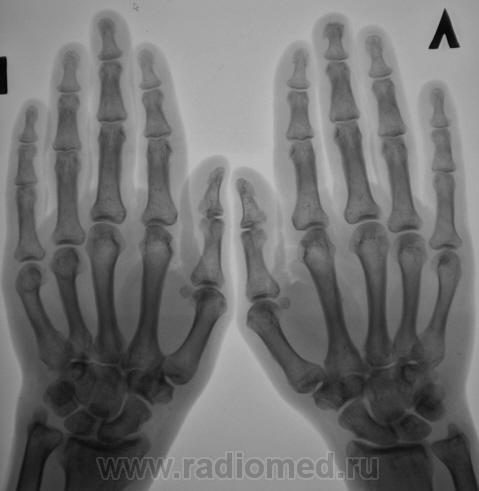

Пол пациента: Женский пол Тип патологии: Другое Область исследования: Скелетно-мышечная система Методы исследования: Rg Пациент с диагнозом "ревматоидный артрит" направлен на рентгенографию кистей. https://radiomed.ru/sites/default/files/styles/case_slider_image/public/user/12/2.pb100037a.jpg?itok=yFjpd1IX https://radiomed.ru/sites/default/files/styles/case_slider_image/public/user/12/3.pb100038.jpg?itok=92itQ56R https://radiomed.ru/sites/default/files/styles/case_slider_image/public/user/12/4.pb100038a.jpg?itok=rsA7mSo8 ID:8677 Чт, 11/11/2010 - 01:03 #1 Makcimalist Не на сайте Был на сайте: 11 лет 8 месяцев назад Зарегистрирован: 08.05.2010 - 14:28 Публикации: 1994 - специфич. признаков начальных стадий РА не нашёл... -------------- "Просто, по видимости, не видеть логики в очевидных вещах - это тоже одно из свойств некоторых умов, наряду с грустными думами о свойствах ума других." © Vega 08/10/2011 Чт, 11/11/2010 - 14:44 #2 Катенёв Валенти... Не на сайте Был на сайте: 7 лет 2 недели назад Зарегистрирован: 22.03.2008 - 22:15 Публикации: 54876 Норму писать? Сб, 13/11/2010 - 01:28 #3 Makcimalist Не на сайте Был на сайте: 11 лет 8 месяцев назад Зарегистрирован: 08.05.2010 - 14:28 Публикации: 1994 Начальные проявления остеоартроза пястно-фаланговых,м/фаланговых суставов... (Норма бывает п/е рождения... и то не всегда...) -------------- "Просто, по видимости, не видеть логики в очевидных вещах - это тоже одно из свойств некоторых умов, наряду с грустными думами о свойствах ума других." © Vega 08/10/2011 Сб, 13/11/2010 - 19:53 #4 Глазков Игорь А... Не на сайте Был на сайте: 9 месяцев 2 недели назад Зарегистрирован: 19.12.2008 - 20:41 Публикации: 1597 Имеются кистовидные просветления костной ткани в эпифизах костей. Прийди к Себе

- специфич. признаков начальных стадий РА не нашёл...

Начальные проявления остеоартроза пястно-фаланговых,м/фаланговых суставов...

Имеются кистовидные просветления костной ткани в эпифизах костей.